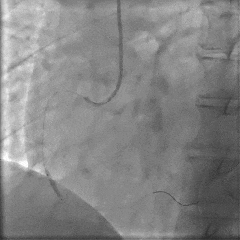

介入治疗过程:将导丝通过右冠脉中远段闭塞病变送至血管远端,送入血栓抽吸导管抽吸出红色血栓,使用球囊对病变处进行预扩张,造影示闭塞病变开通,OCT观察闭塞病变处可见红色血栓及斑块破裂,最小面积3.35mm2。后成功于病变处放置3.0×18mm药物洗脱支架一枚,造影示支架定位良好,未见明显夹层,OCT观察支架贴壁良好,支架内无血栓及夹层影,远端血流TIMI 3级,最小管腔面积5.59mm2。

PCI术后即刻将压力导丝送至RCA远端,测得RCA IMR 63(+),FFR 0.94,表明RCA存在CMD。

冠脉功能学全面评估:

▶ RCA IMR 63(+),FFR 0.94。